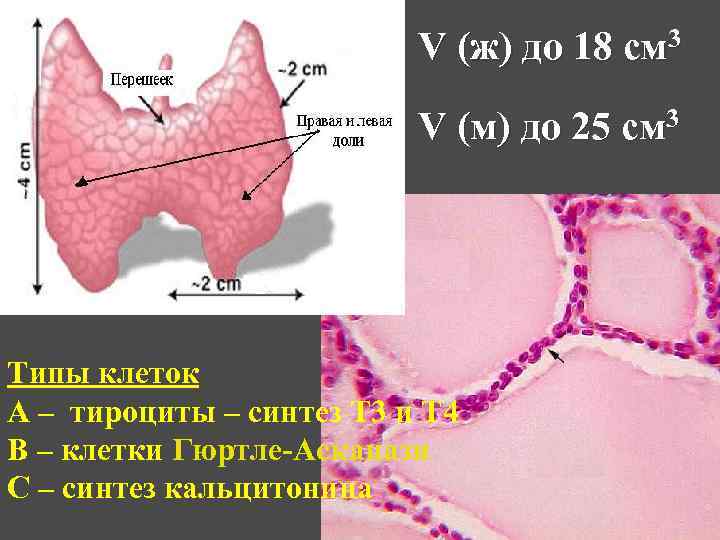

V (ж) до 18 см 3 V (м) до 25 см 3 Типы клеток А – тироциты – синтез Т 3 и Т 4 В – клетки Гюртле-Асканази С – синтез кальцитонина